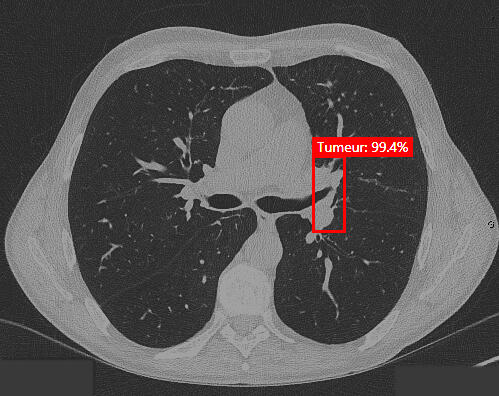

Hekia's AI at the service of medical imaging

Hekia continues to test its artificial intelligence solutions to detect other diseases such as lung, skin and breast cancers. These projects are in their early stages and will require new partnerships, so if you're interested or have a research project to propose, get in touch!